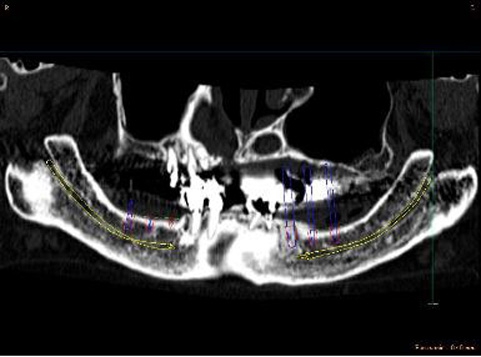

CT撮影から3次元骨モデルを作成し埋入位置の確認